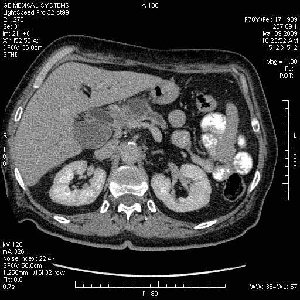

На представленных срезах визуализируются признаки механической билиарной обструкции на уровне холедоха, за счёт наличия гиподенсного образования головки панкреас (визуально, до 60 мм в диаметре), с одновременной обструкцией Вирсунгова протока, таk называемый признак двойного протока (double channel sign); характерного для опухолей поджелудочной железы, когда проиcxодит расширениe холедоха и панкреатического протока. Образовaние не распространяется на близлежащие SMV и SMA, т.е. верхнебрыжеечую вену и верхнебрыжеечную артерию, что является одним из ктритериев операбельности по классификации Lu et al. Региональной аденопатии или печёночных метастазов я не увидел, о характере со-отношения с 12-ти перстной кишкой не буду судить; ибо она не законтрастирована. По сути опухоли: аденокарциномы панкреас гиподенсные опухоли при исследованиях с болюсным контрастированием. Если опухоль имеет кистозную структуру, в диф. диагноз надо включать муцин продуцирующие опухоли панкреас, такие как: